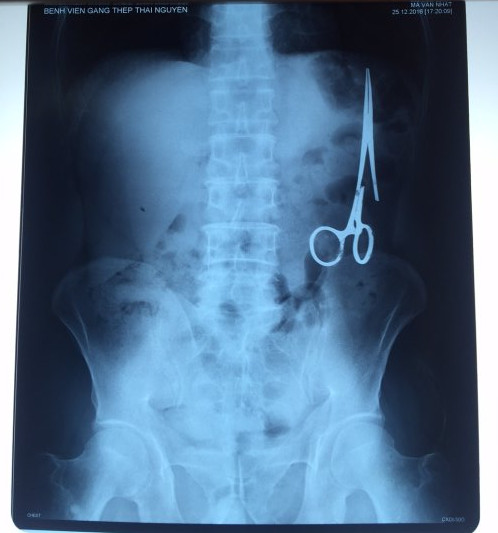

遺留在病人腹中的剪刀

據(jù)越南青年報(bào)1月2日?qǐng)?bào)道,在越南首都河內(nèi)醫(yī)療專(zhuān)家的幫助下,越南東北部的太原?。═hai Nguyen)鑄鋼醫(yī)院的醫(yī)生日前從54歲患者M(jìn).V.N腹中取出一把醫(yī)用剪刀。這把剪刀是此前曾為M.V.N手術(shù)的醫(yī)生遺留的,已經(jīng)在其腹中待了18年時(shí)間。

醫(yī)務(wù)人員表示,這把剪刀遺留在病人腹部左側(cè),與結(jié)腸緊挨著。剪刀的把手已經(jīng)生銹,部分器官也已經(jīng)與剪刀粘連起來(lái)。但在過(guò)去多年中,M.V.N沒(méi)有任何不適感覺(jué),也從未因?yàn)榱粼诟怪械募舻兑l(fā)的相關(guān)問(wèn)題去看過(guò)醫(yī)生。直到2016年12月,M.V.N因?yàn)樵庥隽艘粓?chǎng)車(chē)禍,才到鑄鋼醫(yī)院進(jìn)行身體檢查。

超聲波檢查顯示,M.V.N的腸子中有個(gè)奇怪物體,看起來(lái)就像醫(yī)用剪刀。M.V.N證實(shí),他曾于1998年6月份在北江省綜合醫(yī)院接受手術(shù),在此后也從未進(jìn)行過(guò)任何手術(shù)。近來(lái),他感到腹部有些疼痛,并試圖通過(guò)服用藥物治療。12月27日,M.V.N回到北江省綜合醫(yī)院再次進(jìn)行超聲波檢查,顯示其腹部的確存在怪異物體。